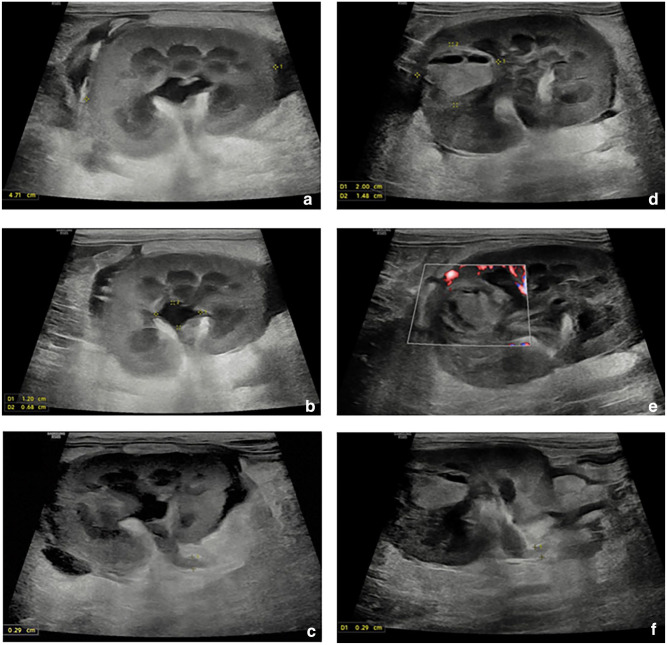

病例总结:一只8个月大的雄性家短毛猫因急性奇异尿症、大便尿症和发声而被报道。患者被诊断为尿道梗阻并住院治疗。出院后36小时,猫开始排出严重的出血性尿,并被诊断为尿腹膜和尿腹膜后。腹部超声和透视逆行阳性对比膀胱输尿管造影未发现尿路破裂的来源。剖腹探查发现双肾漏尿,伴肾盂及肾实质破裂。怀疑无菌肾盂肾炎合并肾出血导致双侧输尿管梗阻,继发尿后腹膜,延伸至尿腹膜。左侧输尿管肾切除术和右侧输尿管皮下旁路置入术作为挽救术;然而,由于预后不良,术中选择安乐死。相关性和新信息:肾盆腔和肾实质破裂是猫尿腹的一个很少报道的原因。此外,虽然严重的肾出血尚未在猫中被描述,但它可能导致双侧输尿管梗阻和尿腹。

Case summary: An 8-month-old male castrated domestic shorthair cat was presented for acute stranguria, pollakiuria and vocalization. The patient was diagnosed with urethral obstruction and hospitalized for medical management. At 36 h after discharge, the cat started passing severely hemorrhagic urine and was diagnosed with a uroperitoneum and uroretroperitoneum. An abdominal ultrasound and fluoroscopic retrograde positive contrast cystourethrogram did not identify a source of urinary tract rupture. An exploratory laparotomy revealed urine leakage from both kidneys, with evidence of rupture involving both the renal pelvis and parenchyma. It is suspected that sterile pyelonephritis and renal hemorrhage resulted in bilateral ureteral obstruction, and subsequent uroretroperitoneum, extending to cause uroperitoneum. Left ureteronephrectomy and right subcutaneous ureteral bypass placement was offered as a salvage procedure; however, euthanasia was elected intraoperatively because of a poor prognosis.